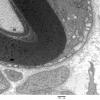

PERIPHERAL NEUROPATHY

7B CIDP (3)